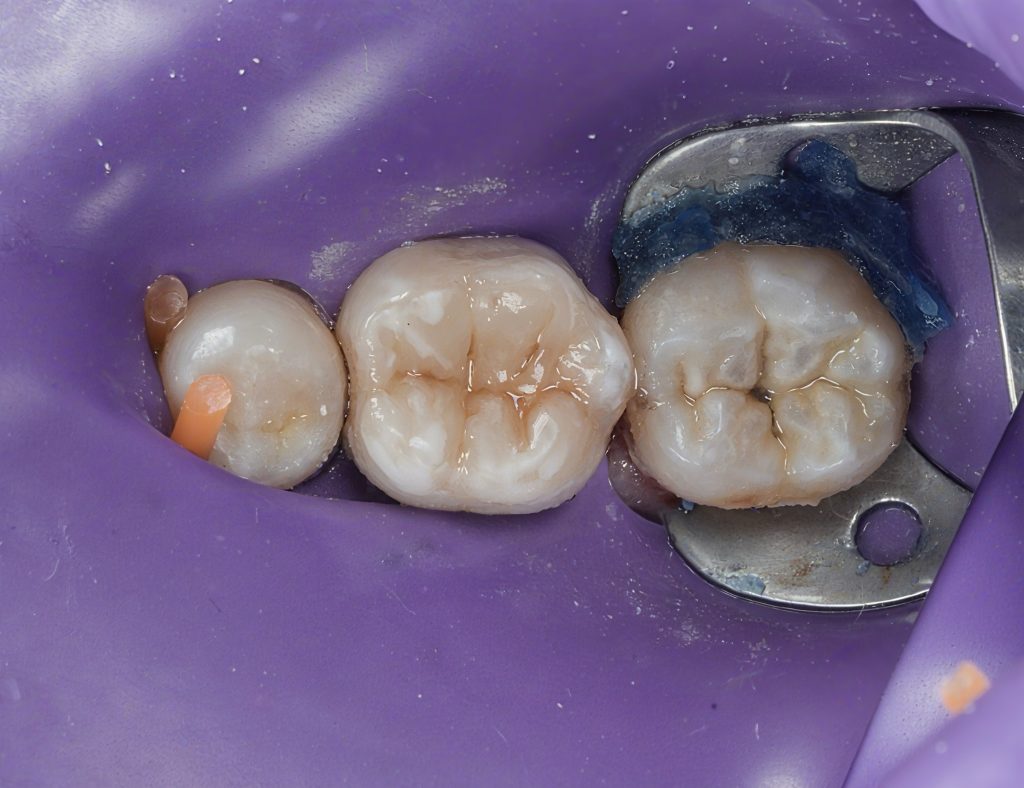

Obturation

Following complete drying of the canals, obturation was performed to achieve a dense, three-dimensional seal. Special care was taken to ensure proper adaptation in the apical and coronal thirds.

A definitive coronal seal was placed immediately after obturation to prevent microleakage.

Cuspal Coverage Restoration

Given the extent of tooth structure loss and the functional demands on mandibular first molars, cuspal coverage was indicated. Occlusal anatomy was rebuilt using a biomimetic approach to restore:

Finishing and polishing were completed to achieve smooth margins and harmonious occlusion.